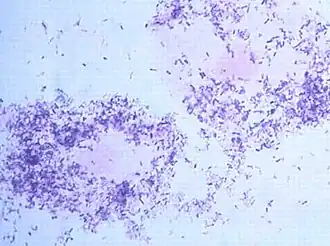

![]() Морфотипы Gardnerella vaginalis во влагалищном мазке, под микроскопом. | |

Баллы Nugent основаны на результатах микроскопии мазка, окрашенного по Граму, с оценкой соотношения различных морфотипов. В настоящее время этот метод считается «золотым стандартом» в диагностике бактериального вагиноза. Ответ выдается в виде баллов от 0 до 10. Нормальное состояние биоценоза влагалища констатируют при 0—3 баллах, при 4—6 баллах — промежуточное состояние, более 6 баллов — бактериальный вагиноз. При анализе не учитываются морфотипы, не связанные с бактериальным вагинозом; клиническая интерпретация промежуточных состояний затруднена.